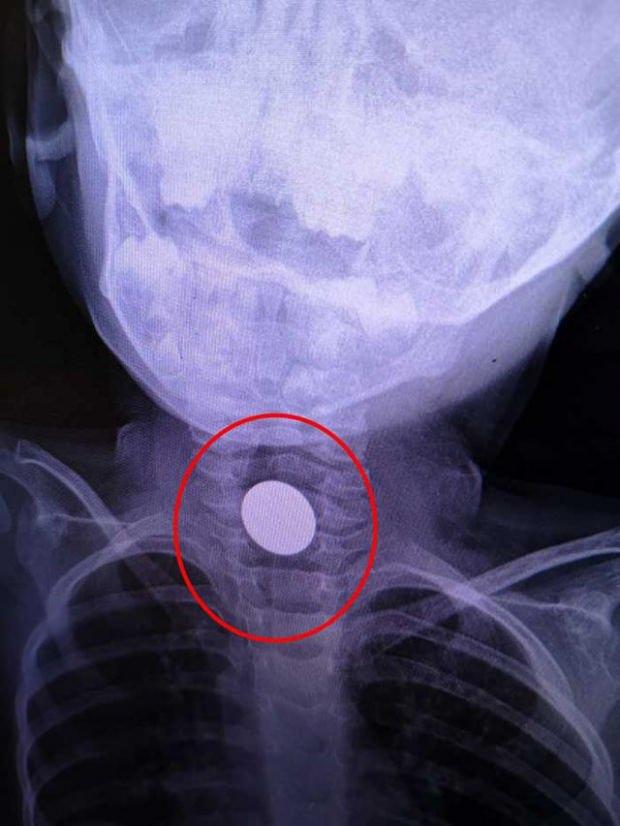

Bursa’nın İnegöl ilçesinde, Hamza K.’nin (3) boğazına takılı kalan madeni 1 lira, hastanede yapılan müdahale ile çıkarıldı

Bursa’nın İnegöl ilçesi Süleymaniye Mahallesi’nde yaşayan Mevlüt ve Hilal K. çiftinin oğulları Hamza, salonda bulduğu madeni 1 lirayı ağzına attı. Ancak para, çocuğun boğazına takıldı.

Hamza hemen İnegöl Devlet Hastanesi’ne götürüldü. Burada yapılan ilk müdahalenin ardından da Dörtçelik Çocuk Hastanesi’ne sevk edildi.

Para, yapılan operasyon ile çıkarıldı. Çocuğun sağlık durumunun iyi olduğu öğrenildi.